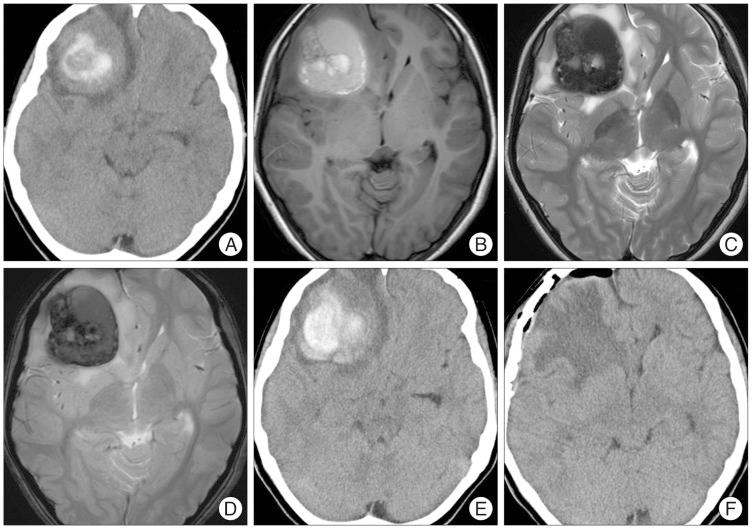

Chronic encapsulated intracerebral hematoma (CEIH) is a rare cerebrovascular disease that behaves as a slowly expanding lesion with a gradual onset. It is well established that CEIH is associated with arteriovenous malformations; however, CEIH associated with cavernous malformation (CM) is extremely rare. We herein report a case of CEIH associated with CM, and discuss its pathogenesis. A 12-year-old female was admitted to our hospital because of a one week history of progressive headache and nausea. Brain computed tomography scan and magnetic resonance imaging showed an intracerebral hematoma surrounded by edema in the right frontal lobe. One week later, her headache and nausea worsened, and a brain computed tomography scan revealed the enlargement of hematoma. A right frontal craniotomy was performed. The capsule, mass, and hematoma were totally removed. Histological examination confirmed the diagnosis of CEIH associated with CM. Immunohistochemical analysis revealed increased expression of vascular endothelial growth factor (VEGF) and the VEGF receptor-1 in the endothelium and fibroblasts. Our findings suggest that the activated VEGF pathway might have positively contributed to development of CEIH in the present patient.

慢性包裹性脑内血肿(CEIH)是一种罕见的脑血管疾病,表现为起病隐匿、缓慢扩大的病灶。目前已明确CEIH与动静脉畸形有关;然而,与海绵状畸形(CM)相关的CEIH极为罕见。我们在此报告一例与CM相关的CEIH病例,并讨论其发病机制。一名12岁女性因进行性头痛和恶心一周入院。脑部计算机断层扫描和磁共振成像显示右额叶有一个被水肿包围的脑内血肿。一周后,她的头痛和恶心加重,脑部计算机断层扫描显示血肿增大。遂行右额开颅手术。完整切除包膜、肿块和血肿。组织学检查确诊为与CM相关的CEIH。免疫组织化学分析显示血管内皮生长因子(VEGF)及其受体-1在内皮细胞和成纤维细胞中的表达增加。我们的研究结果表明,激活的VEGF途径可能对本患者CEIH的发展起到了积极作用。